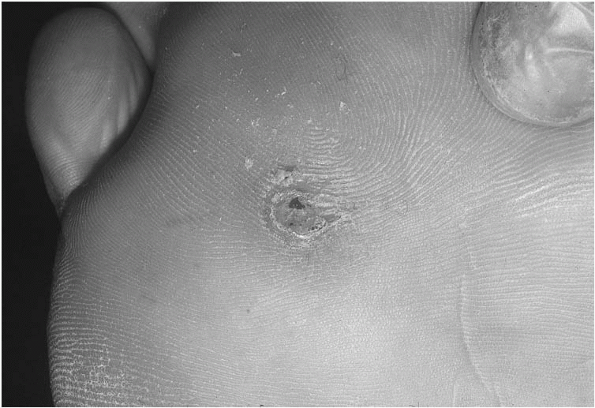

The classic description of the lesions of herpes is grouped vesicles on an erythematous base (Fig. 13-1).

The vesicles contain clear to serosanguineous fluid and may coalesce with adjacent vesicles to form larger lesions.

The virus is contained within the fluid of the vesicle, and therefore these vesicles are considered contagious.

The skin under the vesicles tends to be erythematous but this does not extend far beyond the lesions.

The vesicles rupture in a few days forming shallow erosions covered by a yellowish crust.

These erosions will then heal in 8 to 14 days.

Figure 13-1

Herpes simplex : grouped vesicles on an erythematous base. (From Goodheart HP. Goodheart’s Photoguide of Common Skin Disorders, 2nd ed. Philadelphia: Lippincott Williams & Wilkins, 2003.)  |